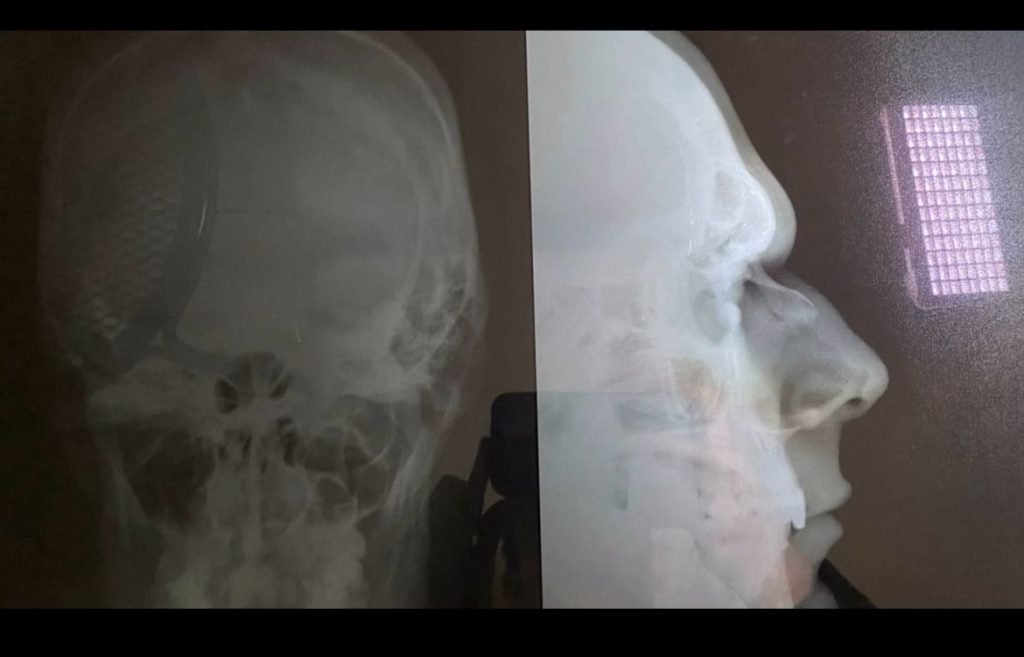

El reconocido farandulero y abogado Carlos Viveros encendió las redes sociales tras publicar un contundente mensaje acompañado de una radiografía que revela los estragos sufridos en su cabeza y nariz tras un altercado en una exclusiva discoteca de Asunción.

En una entrevista con el periodista Ronald para el programa “No son ángeles”, Viveros relató con detalle el incidente que lo dejó con graves lesiones, mientras mostraba las pruebas médicas que respaldan su denuncia.